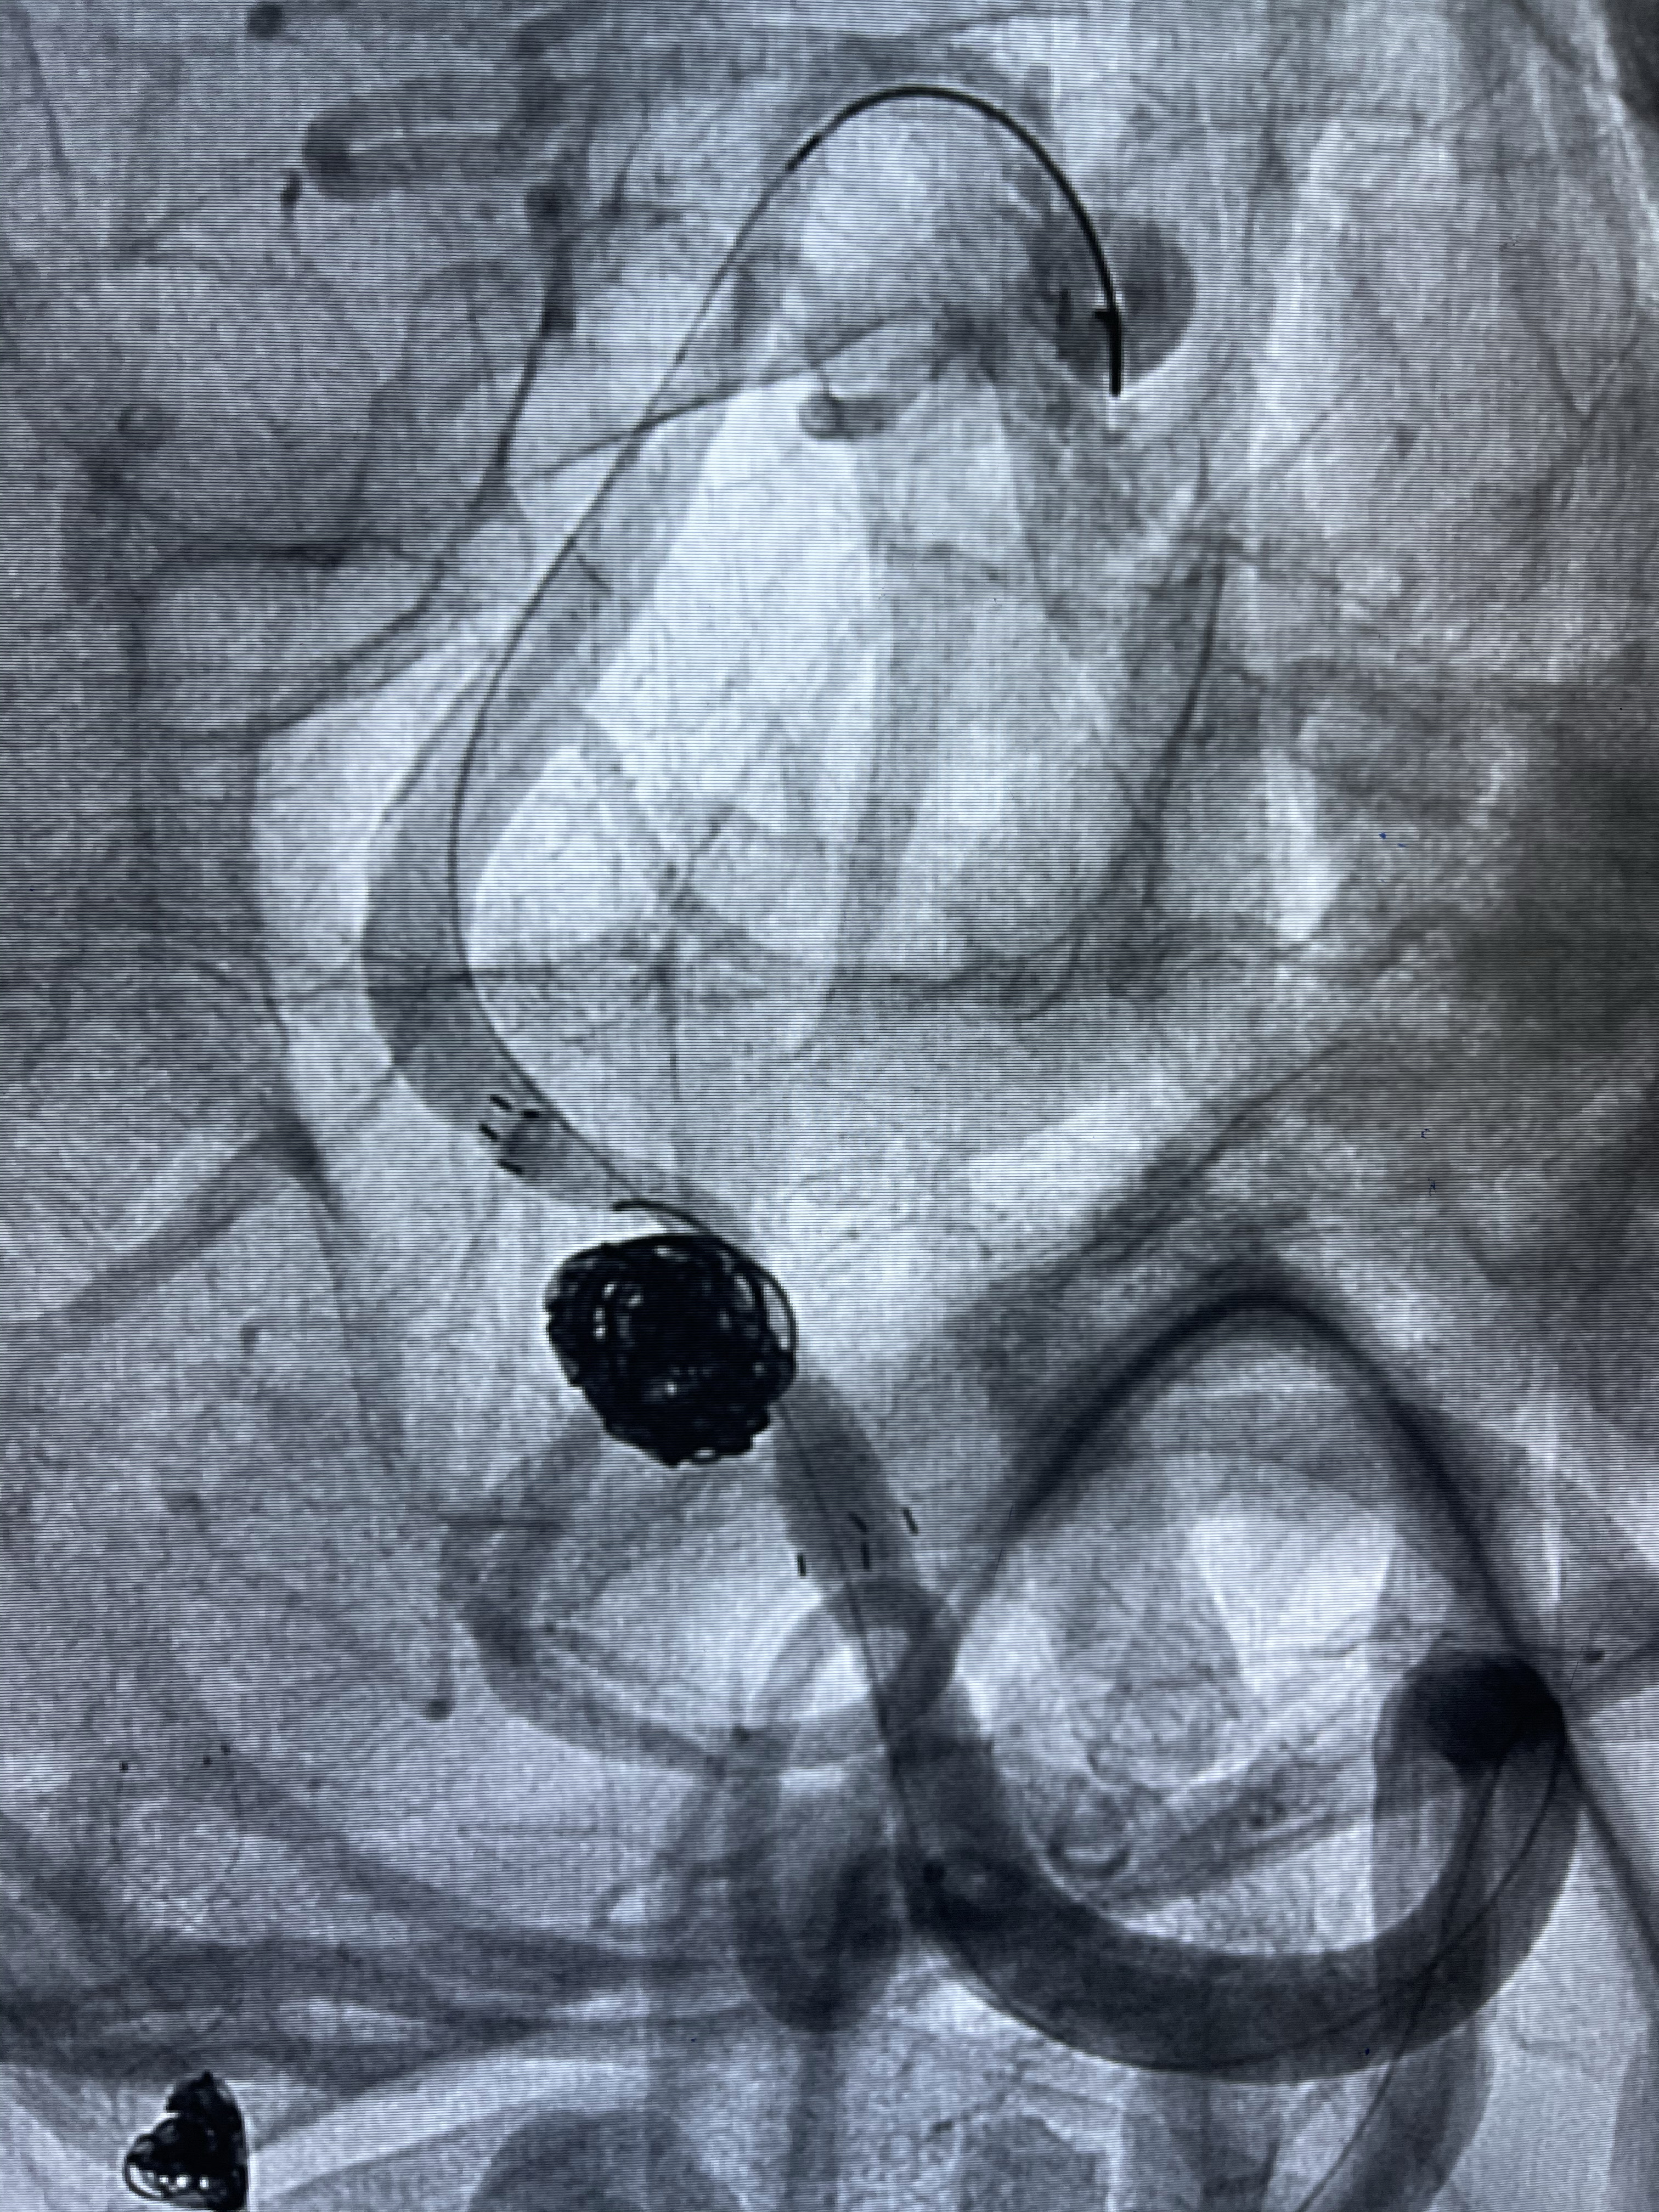

支架释放,透视下

1.Enterprise4.0-23mm;

2.Tubridge3.5-30mm密网支架